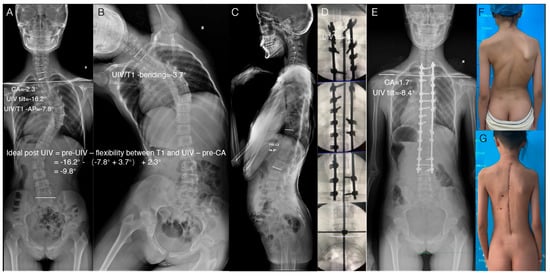

2.4. Verification of the Feasibility of This Method in Clinical Practice